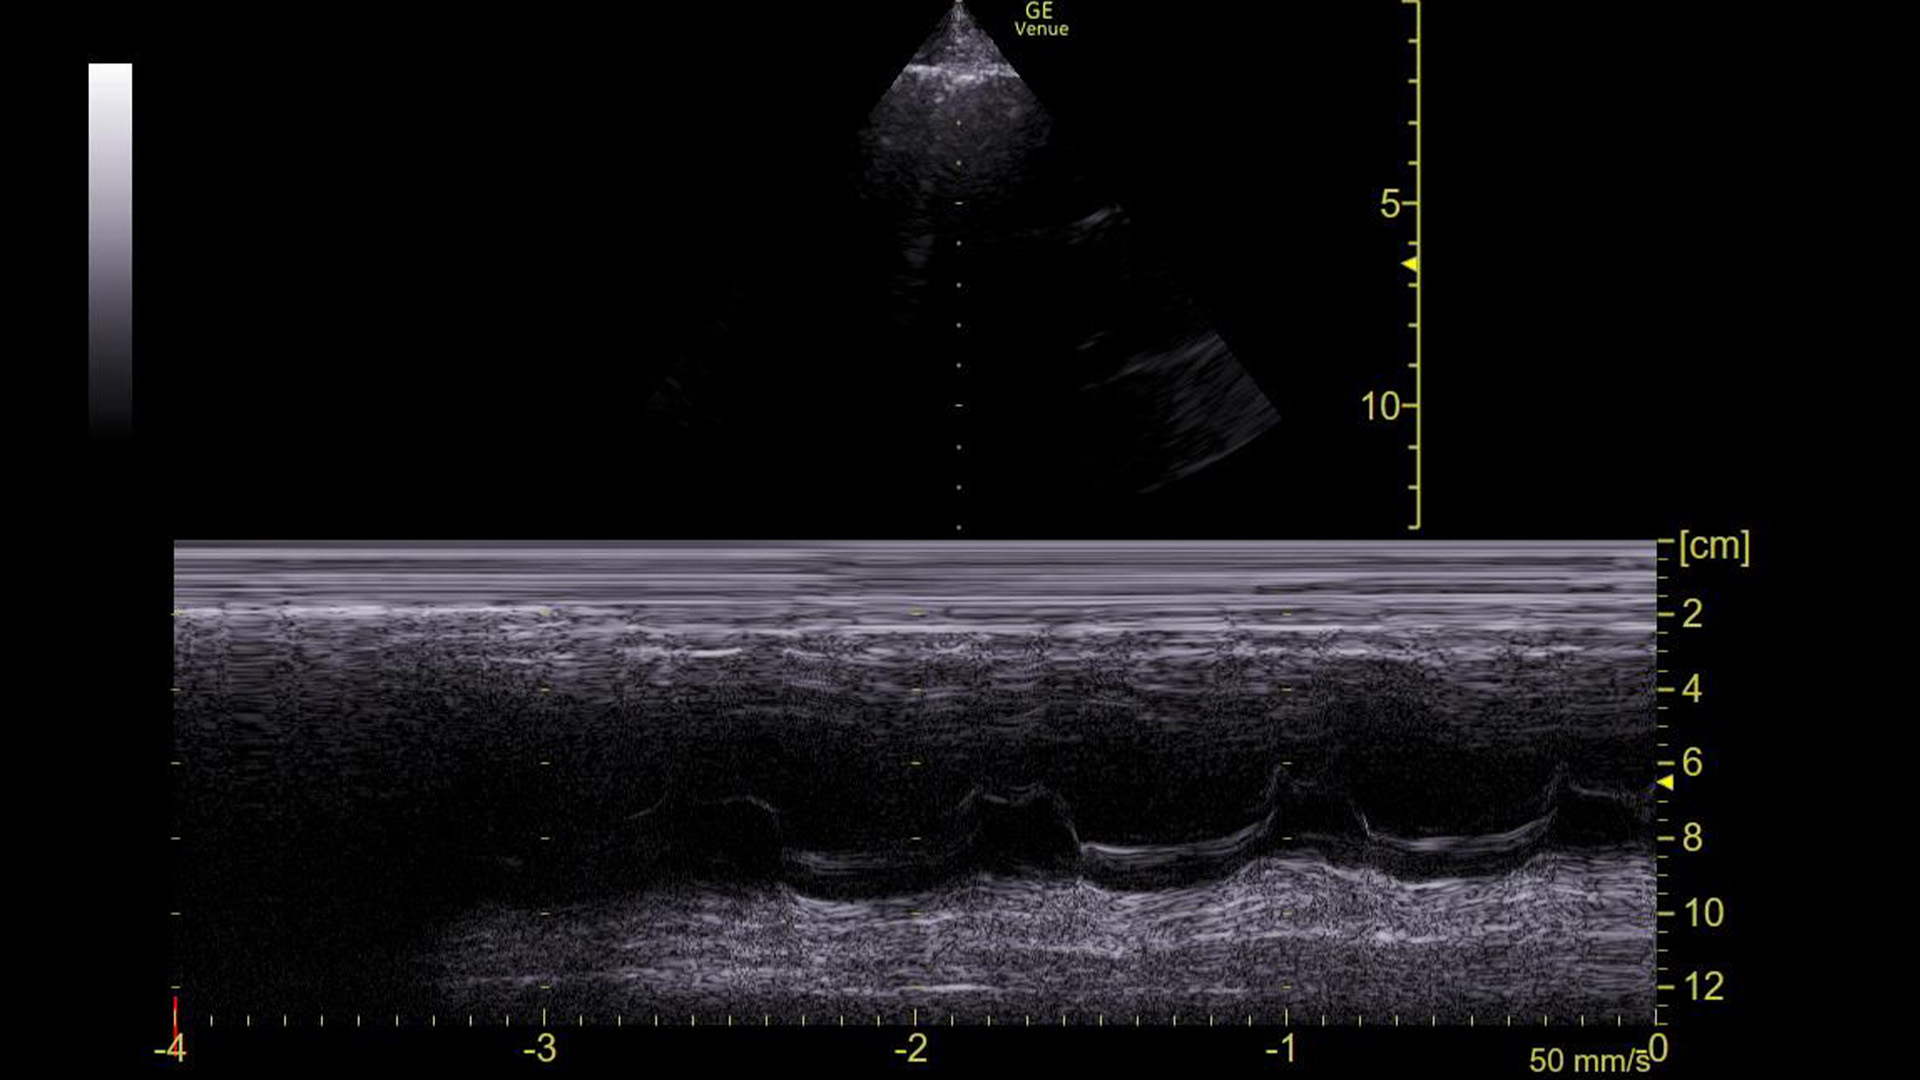

The machine read the ECG as sinus tachycardia, but I had my doubts. So, we obtained this M-mode tracing with the spike over the mitral valve in a parasternal long axis view.

This made it clear that he was in an arrhythmia. The rate was 153, so we assumed it is atrial flutter with 2:1 conduction, but just based on this image and the narrow QRS complex on the ECG, it could have been SVT or a strangely regular atrial fibrillation.

The question is, how did we know that based on this tracing?

Here it is with the area of interest highlighted.

What we are looking at here is the movement of the mitral valve within the left ventricle – specifically what is highlighted in yellow is the movement of the anterior leaflet of the mitral valve. (Recall that it has two leaflets: anterior and posterior.)

You can see that the leaflet flaps once per cardiac contraction. That, however, is ABNORMAL!